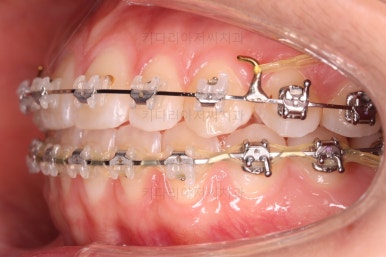

각각 왼쪽, 오른쪽의 교합의 모습입니다.

가장 좋은 교합은 위아래 치아들이 지그재그로 톱니바퀴 물리듯이 맞아들어가야 하는데 오른쪽 사진들 보면 중간중간 빈틈도 많이 보여요.

이런 교합은 장기적으로 치아 수명을 단축시킬 수 있습니다.